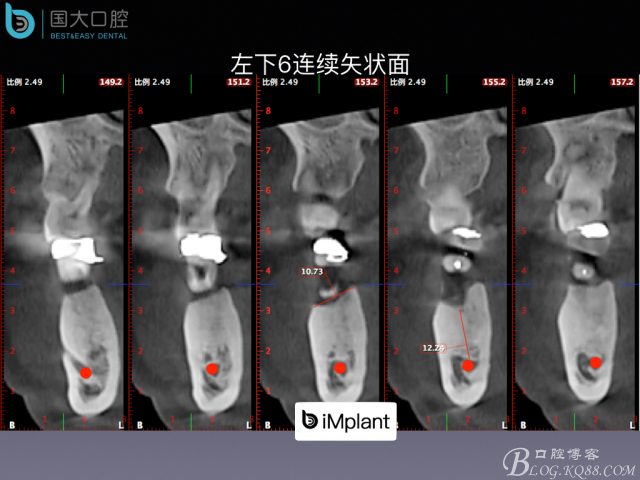

嚴(yán)重根尖周炎能做即刻種植嗎?